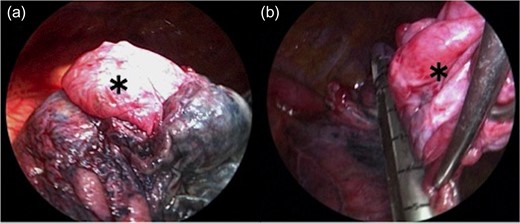

The bulla (*) wall in the apex of the lung was very thin (a). Following left lower lobectomy, the resection of emphysematous bullae (*) was performed (b).

Left lower lobectomy and lymph node dissection were performed. Preoperative computed tomography imaging revealed multiple bullae in the apex of the left lung and very thin bullae walls (Fig. 2A). Concerned that the patient would develop a second primary lung cancer or pneumothorax in the future, we simultaneously performed a bullectomy for two bullae with a lobectomy (Fig. 2B). Because the patient’s lung was highly emphysematous, linear staplers with PGA felt (Endo GIA™ Reinforced Reload with Tri-Staple™ Technology, cartridge color: purple, MEDTRONIC, Tokyo, Japan) were used for the bullectomy. We confirmed the absence of bleeding in the thoracic cavity and completed the operation (Video 1). The drainage from the thoracic tube turned bloody beginning 1 h after the operation. The drainage volume increased, and 600 ml of bodily drainage was observed for 2 h after the drainage had turned bloody. A chest X-ray imaging examination was performed, which confirmed fluid accumulation in the left thoracic cavity (Fig. 3). Because the patient’s anemia had also progressed, as compared with preoperative measurements (preoperative hemoglobin, 12.8 g/dl; 3-h postoperative hemoglobin, 9.1 g/dl), we determined that sustained bleeding had occurred in the thoracic cavity; we subsequently decided to carry out a reoperation to perform hemostasis. No air leakage was observed during the period between both operations.